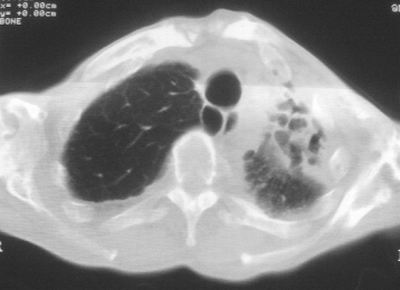

标题: CT11864:男,47岁,反复咳嗽、咯痰、咯血3年,请分析. [打印本页]

患者,男,47岁,反复咳嗽、咯痰、咯血3年,再发5天。痰培养未找到真菌、抗酸杆菌、癌细胞。

左肺上叶体积明显缩小,其内见多发透光区,纵隔向左侧移位,左肺下叶多发班片状病灶,边界模糊,1左肺上叶先天肺发育不全,2左肺下叶肺炎,

左肺上叶结核伴肺纤维化,纵隔移位,左肺下叶感染性病变,建议抗炎抗结核后复查,双肺气肿.

以下是引用xulianj在2008-2-25 21:01:00的发言:[br]左肺上叶结核伴肺纤维化有霉菌球形成,纵隔移位,左肺下叶感染性病变,建议抗炎抗结核后复查,双肺气肿.

考虑:左肺慢纤伴霉菌球形成、双肺全小叶型肺气肿。

1)考虑为:左肺上叶肺结核(空洞形成),伴左下肺感染;不排除霉菌感染可能。2)肺气肿。

左肺上叶结核伴肺纤维化空洞形成并左肺下叶感染,纵隔牵拉移位,建议作进一步检查排除左侧肺霉菌感染可能。